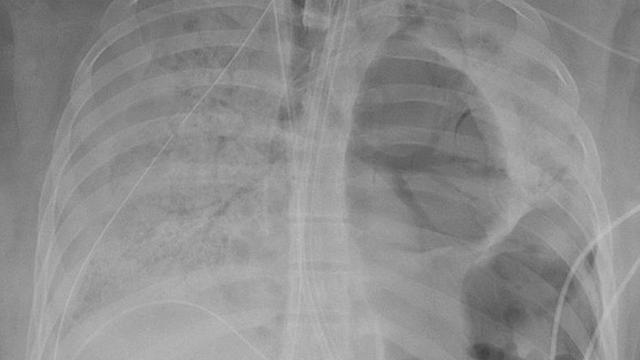

Liputan6.com, Jakarta - Sebuah rumah sakit di Amerika Serikat telah merilis foto mengerikan paru-paru wanita muda dan sehat yang dirusak oleh virus Corona. Pasein yang usianya dua puluhan itu memiliki organ vital yang diambil dalam operasi transplantasi paru-paru yang langka setelah nyawanya terancam akibat virus tersebut.

Gambar yang dirilis oleh Northwestern Medicine itu menunjukkan bagaimana virus Corona merusak paru-parunya. Sementara transplantasi ganda itu sendiri dilakukan di Northwestern Memorial Hospital di Chicago.

Ahli bedah merilis rincian kasus untuk menunjukkan kepada petugas medis lainnya di seluruh dunia bahwa transplantasi paru-paru bisa menjadi pilihan yang layak untuk beberapa pasien virus Corona yang sakit parah. Pasien yang digambarkan sebagai wanita muda Hispanik berusia dua puluhan itu, pulih setelah prosedur transplantasi.